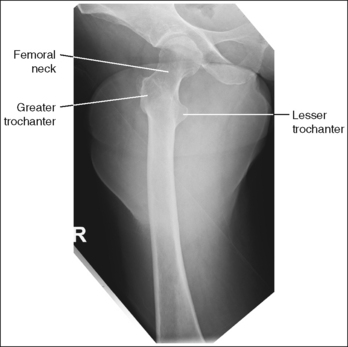

See Figures 6-103 and 6-104 and Boxes 6-21 and 6-22.

Image density is uniform across the femur.

• Position the thicker proximal femur at the cathode end of the tube and the thinner distal femur at the anode end to take advantage of the anode heel effect and obtain more uniform density across the femur.

The distal femur demonstrates an AP projection. The medial and lateral femoral epicondyles are in profile, the femoral condyles are symmetrical in shape, and the tibia is superimposed over 0.25 inch (0.6 cm) of the fibular head.

• To obtain an AP distal femoral projection, place the patient in a supine position with the knee fully extended. Internally rotate the leg until the foot is rotated to a 15- to 20-degree angle and an imaginary line drawn between the medial and lateral femoral epicondyles is positioned parallel with the IR (Figures 6-105 and 6-106). This positioning places the medial and lateral femoral epicondyles at equal distances from the IR, as well as medially and laterally in profile, respectively. It also centers the intercondylar eminence within the intercondylar fossa.

• Effect of leg rotation. If the femoral epicondyles are not positioned parallel with the IR, an AP projection has not been obtained. If the leg was not externally (laterally) rotated enough to place the epicondyles at equal distances from the IR, the epicondyles are not in profile, the medial femoral condyle is larger than the lateral condyle, and the tibia is superimposed over more than 0.25 inch (0.6 cm) of the fibular head (see Image 92). If the leg was internally (medially) rotated more than needed to place the femoral epicondyles at equal distances from the IR, the epicondyles are not demonstrated in profile, the lateral femoral condyle is larger than the medial condyle, and the tibia is superimposed over less than 0.25 inch (0.6 cm) of the fibular head (see Image 93).

• Positioning for femoral fracture. When a patient has a fractured femur, the leg should not be internally rotated, but left as is. Forced internal rotation of a fractured femur may injure the blood vessels and nerves that surround the injured area. Because the leg is not internally rotated when a fracture is in question, the distal femur demonstrates external rotation.